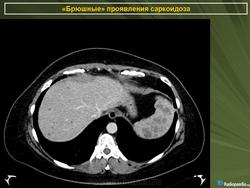

Саркоидоз селезенки и печени

Хотя саркоидоз печени и/или селезёнки обычно протекает бессимптомно, а увеличение уровня ферментов печени может быть небольшим, по данным исследователей из Японии методы визуализации (УЗИ брюшной полости, РКТ, ЯМР-томография и сканирование с галлием и технецием) могут легко выявить патологию. При лапароскопии можно видеть множественные узелки по поверхности печени или селезёнки, биопсия которых выявляет неказеифицированные эпителиоидные гранулёмы, содержащие многоядерные гигантские клетки, что особенно часто обнаруживают в области ворот органа (Kitamura M., Ishizaki T., 1994).

По мнению греческих рентгенологов очаговые изменения в селезёнке и печени являются необычными проявлениями абдоминального саркоидоза. Они описали случай саркоидоза, когда имелись множественные очаговые изменения пониженной плотности в печени и селезёнки на РКТ органов брюшной полости при нормальной рентгенограмме органов грудной клетки. Диагноз был подтверждён биопсией печени (Thanos L. et al., 2002).